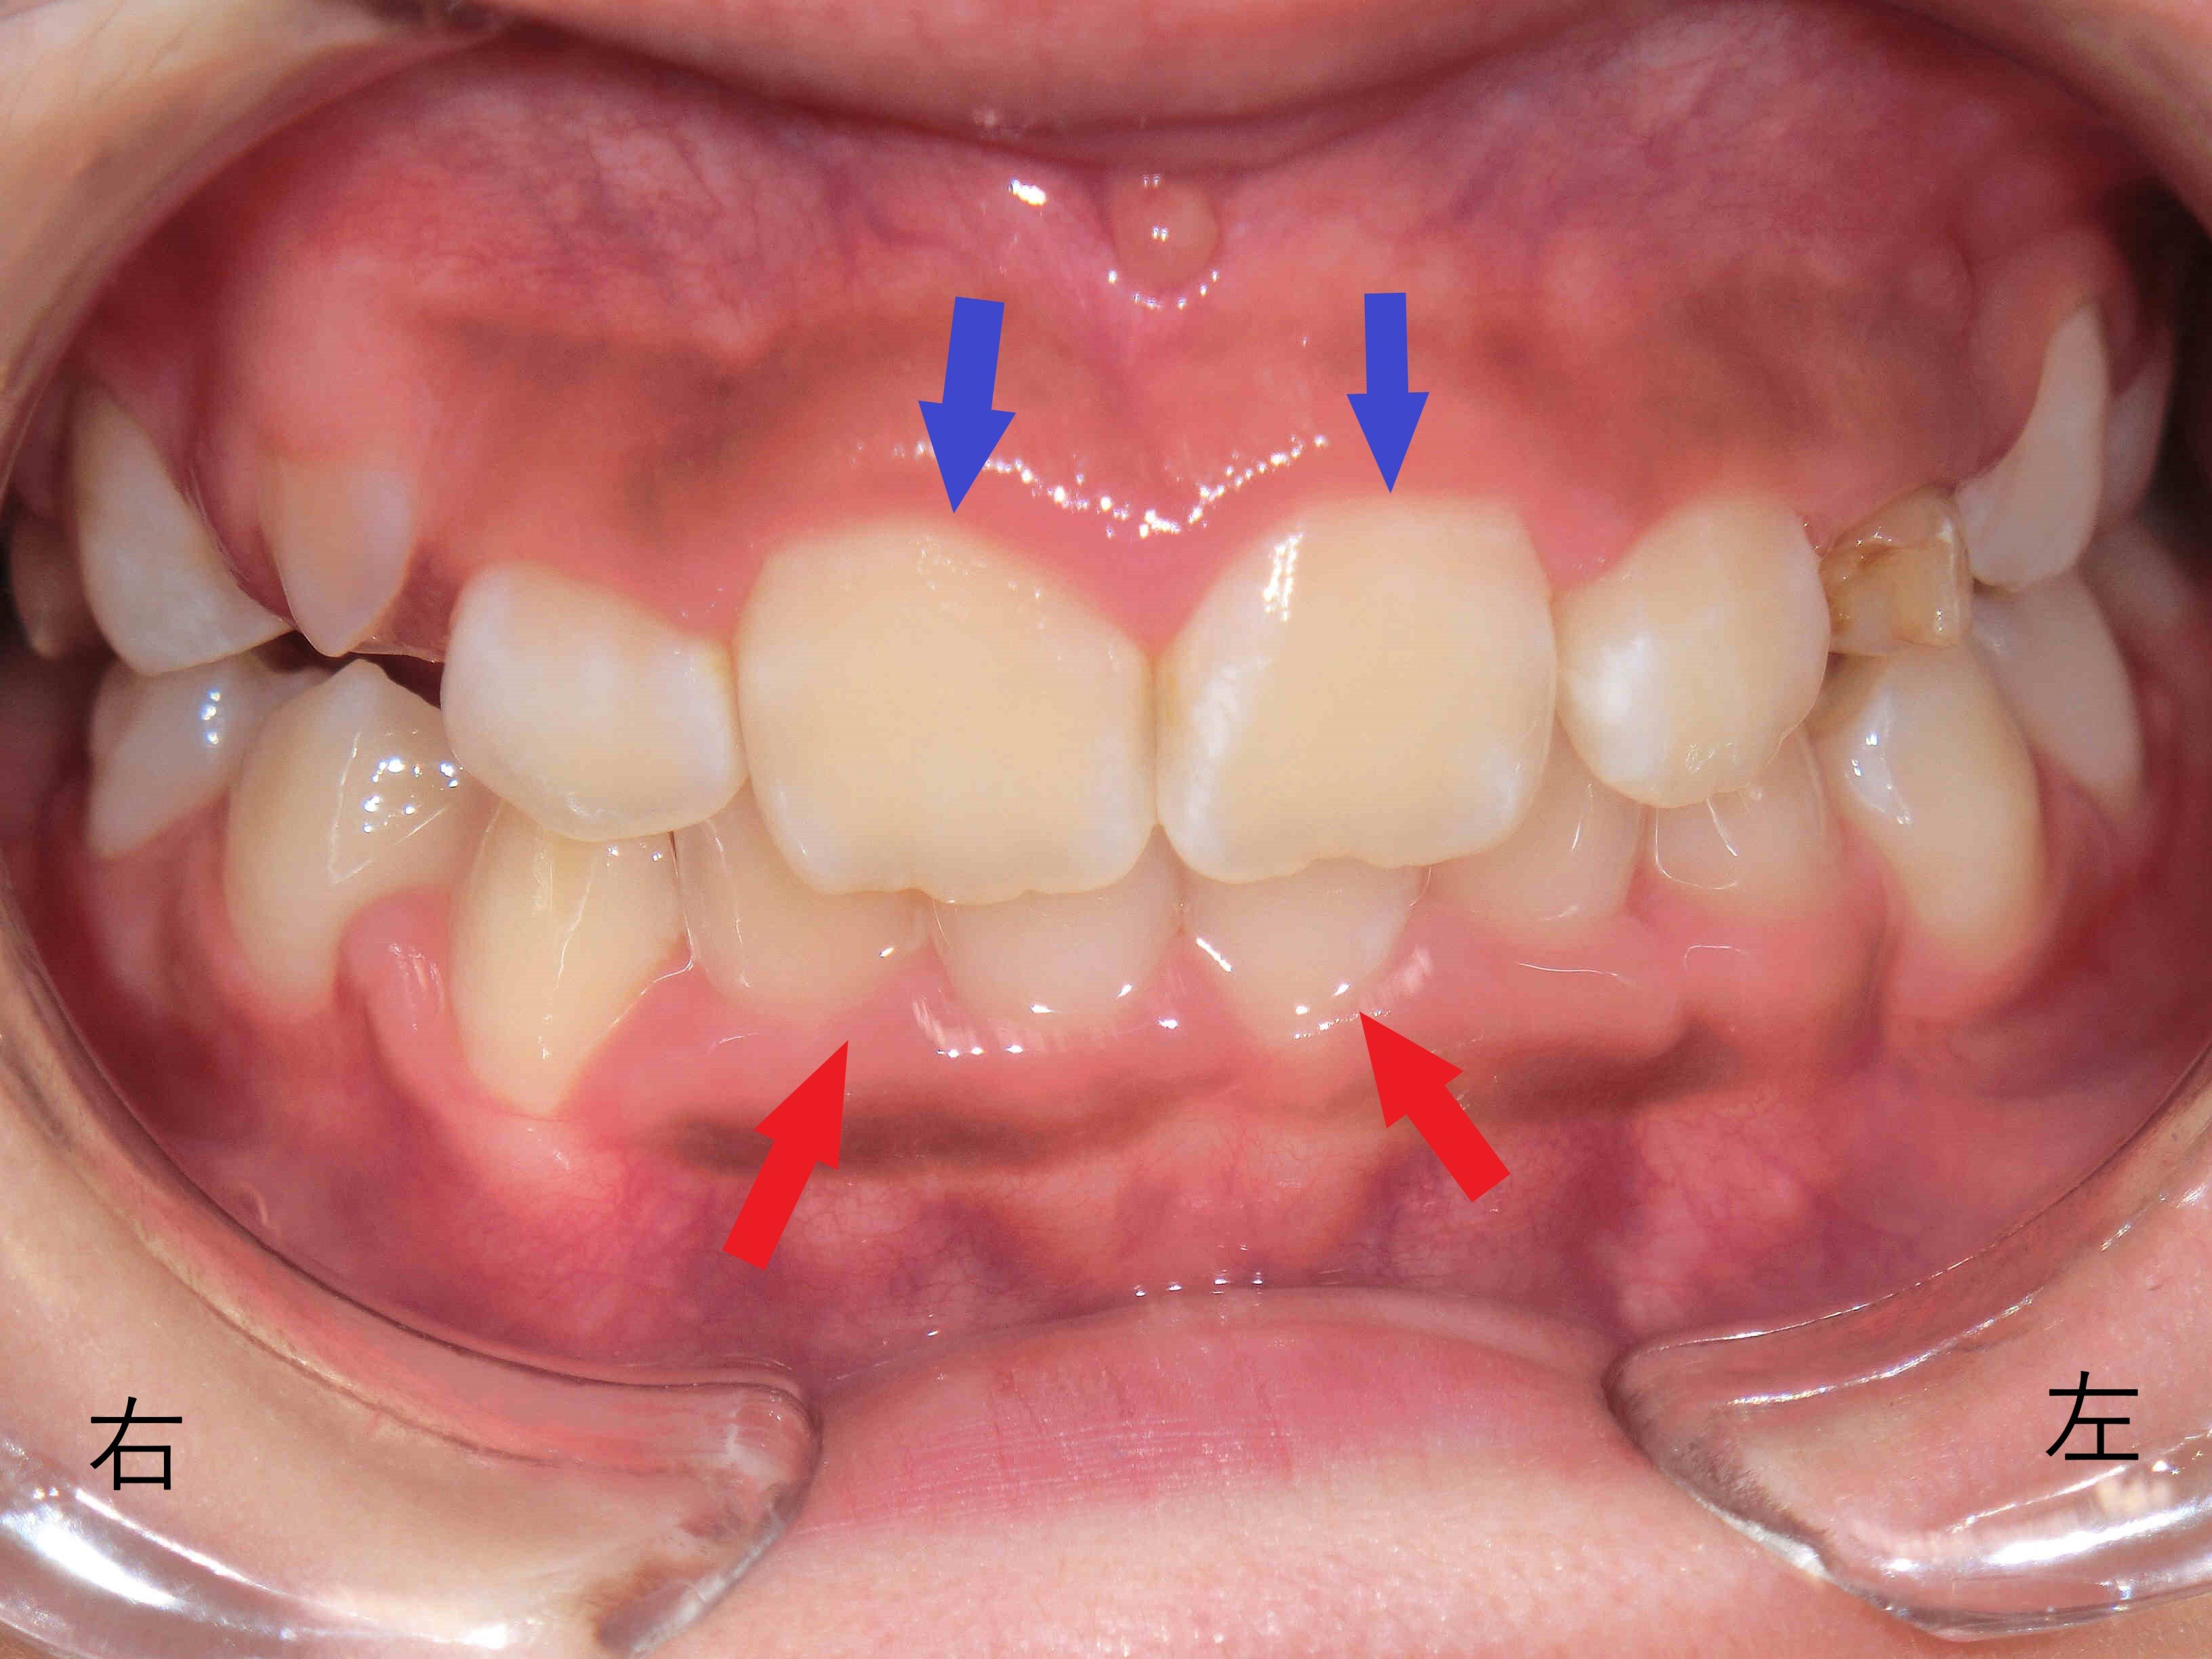

治療開始から12か月後(11歳6か月時)には、上下歯列の拡大が進行し、下顎の前下方への成長が確認されました。これにより、上顎前歯で隠れる下顎前歯の範囲が減少し、浅い噛み合わせが形成されつつあります。

しかし、当時はまだ混合歯列期であり、左右の上顎犬歯が正常な位置に萌出するかどうかが治療の鍵でした。

・ 11歳6か月時:上顎の拡大が進んでいたものの、左上乳犬歯が残存しており、犬歯の萌出スペースが不足